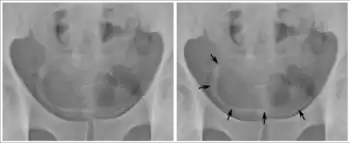

Eggs can become lodged in the liver,[31] leading to portal hypertension, splenomegaly, the buildup of fluid in the abdomen, and potentially life-threatening dilations or swollen areas in the esophagus or gastrointestinal tract that can tear and bleed profusely (esophageal varices). This condition can be separated into two distinct phases: inflammatory hepatic schistosomiasis (early inflammatory reaction) and chronic hepatic schistosomiasis. Most common species to cause this condition are S. mansoni, S. japonicum, and S. mekongi.

Imaging modalities such as X-rays, ultrasound, computed tomography (CT), and magnetic resonance imaging (MRI) can be utilized to evaluate for severity of schistosomiasis and damages of the infected organs.[53] For example, X-ray and CT scans of the chest can be used to detect lesions in the lungs from pulmonary schistosomiasis, and pelvic X-ray can reveal calcification of the bladder in chronic urinary schistosomiasis.[53] Ultrasound may be used to look for abnormalities in the liver and spleen in hepatosplenic schistosomiasis, and CT scan of the liver is a good tool to look for calcification in the liver associated with S. japonicum infection.[53] CT scan can also be used to assess damages from the schistosomiasis infection in the intestinal, urogenital, and central nervous system.[53] MRI is used to evaluate schistosomiasis of the central nervous system, liver, and genital.[53]